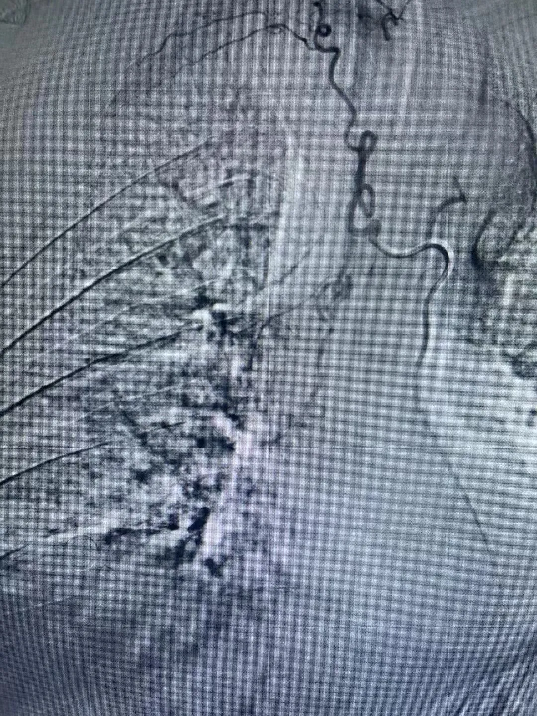

醫院呼吸內科團隊高(gāo)度重視患者的治療,組織全科人員討論(lùn)製定個性化治療方案,通過患者體動脈cta造影檢查,明確了包括支氣管動脈在內的5支病變血管。經充分術前準備,7月2日晚7點,曹辛瑜(yú)副主任在術中(zhōng)精準定位出血病變血管,及時用栓塞劑對病變血管逐個栓塞,完全阻斷病變血管(guǎn)血流,痰液立即恢複正常。患者手術(shù)順利,術後恢複良好。支氣(qì)管動脈栓塞術的應用,大大縮短患(huàn)者住(zhù)院時間,且有(yǒu)效降低患者出現大咯血窒息死亡風險。